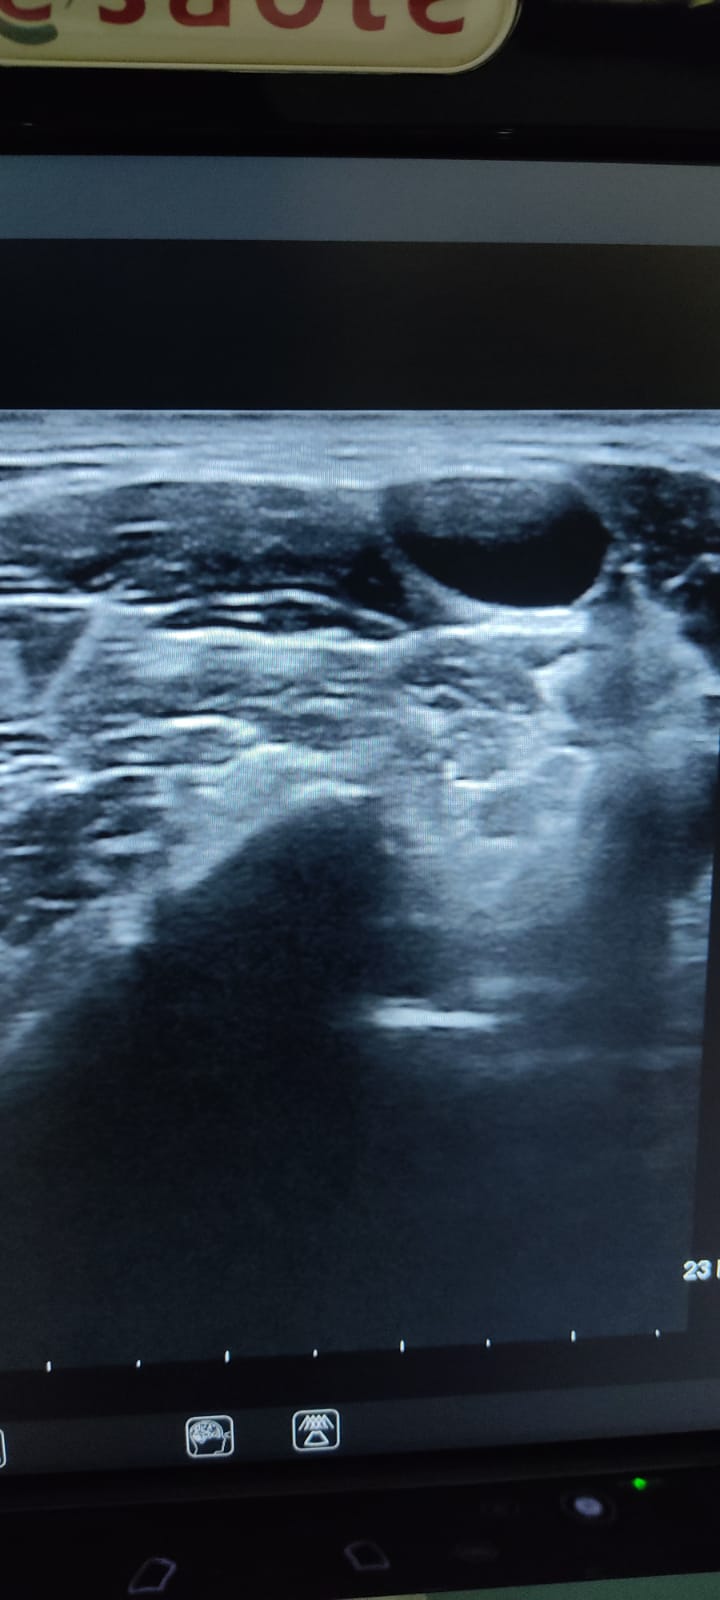

Se le realiza una Ecografía clínica a pie de cama (POCUS), donde se observan múltiples adenopatías anecoicas en ambas cadenas submandibulares y laterocervicales, algunas de 3 cm aproximadamente, de aspecto redondeado y con sugestiva presencia de hilio.

En LTI, se observa nódulo espongiforme en su parte superior sólido con calcificaciones en región inferior de más de 2 cm de diámetro superior, más alto que ancho con calcificaciones groseras, presentando otro nódulo de similares características en cara posterior de LTD. Todo ello, es sugestivo de TIRADS 5.